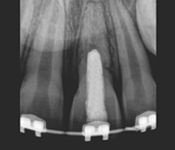

Pictured: Preoperative and Postoperative

Our patient presented with severe pain and required emergency root canal treatment. After cleaning and removing the inflamed pulp, the root canal system was successfully restored and the natural tooth saved.